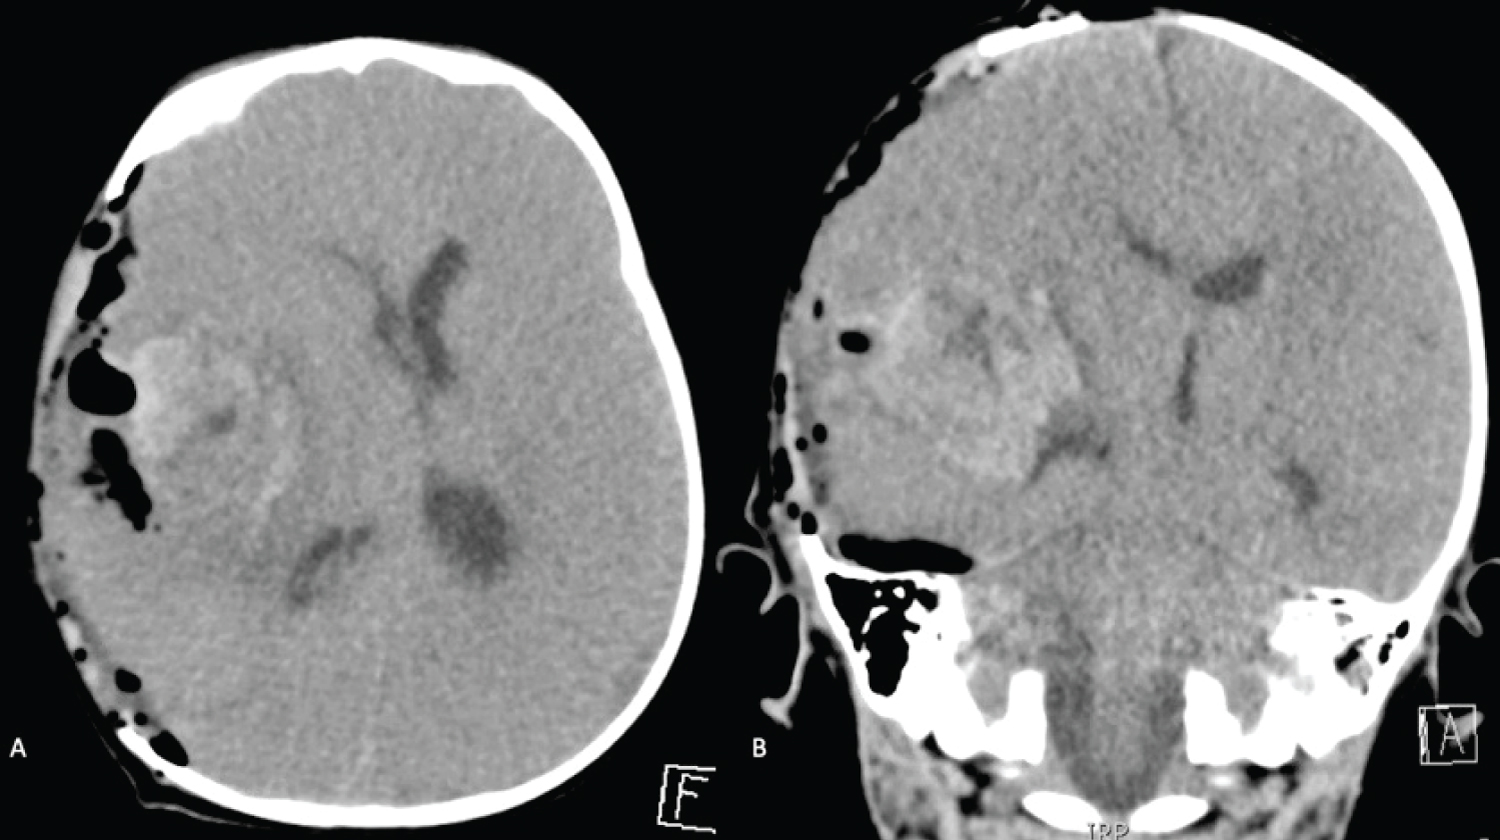

A cranioplasty was performed on POD 14, as the flap was sufficiently soft. Preoperatively he was bolused 500 IU of Factor VIII and continued on 500 IU every six hours. The following day his Factor VIII activity level was found to be 323%, and his dose was adjusted back to 250 IU every six hours. There was no evidence of active bleeding or extravasation from the wound site, and the dressing was removed on POD 2. There were no further complications after the cranioplasty (Figure 6), or deterioration in neurological status. Figure 7 summarizes clotting factor concentrate administered in the perioperative period.

Figure 6: Post-cranioplasty non-contrast axial CT images demonstrating post-operative changes. Improved mid-line shift, and stable ventricular size. View Figure 6